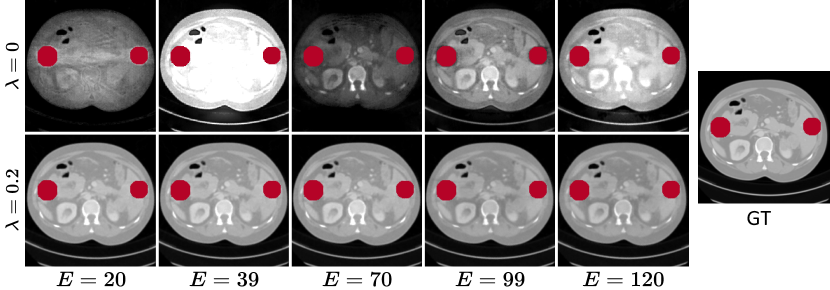

Refer to caption

Figure 5: Qualitative comparison of the CT images at different energy levels using our Polyner model without (Top Row) and with (Bottom Row) the EDS loss EDSsubscriptEDS\mathcal{L}_{\text{EDS}} on a sample (##\#4) of the DeepLesion dataset [43]. The red regions denote metals.

Influence of Energy-dependent Smooth Loss. We investigate the influence of the EDS loss on the model performance. To this end, we set different weights λ{0,0.1,0.2,0.3,0.4}𝜆00.10.20.30.4\lambda\in\{0,0.1,0.2,0.3,0.4\} for the EDS loss in Eq. (9). We show the quantitative results in Table 3. The model performance initially improves with an increasing contribution of the EDS loss but later slightly degrades if its contribution keeps increasing. The best performance is obtained at λ=0.2𝜆0.2\lambda=0.2. This is because the absence of the EDS loss cannot ensure the smooth changes of the LACs of the body over energy levels. However, excessive bias towards it can result in the forward model degrading as a linear integral transformation, where the polychromatic LACs across all energy levels are identical. Fig. 5 shows the qualitative results. We observe that the CT images at different energy levels randomly change when the EDS loss is not used. In contrast, the regularization can effectively ensure the changes in the LACs are smooth. Moreover, the LACs slowly decrease as the X-ray energy level increases, which is generally consistent with the experimental findings reported in previous works [50].